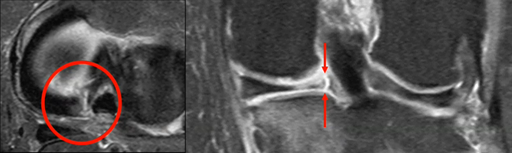

Genou  anatomie, lésions méniscales, arthrose typique atypique, SONK…

ACID S. – UCL

Année académique 2022-2023

Musculo-squelettique Genou DES SPECIALITE